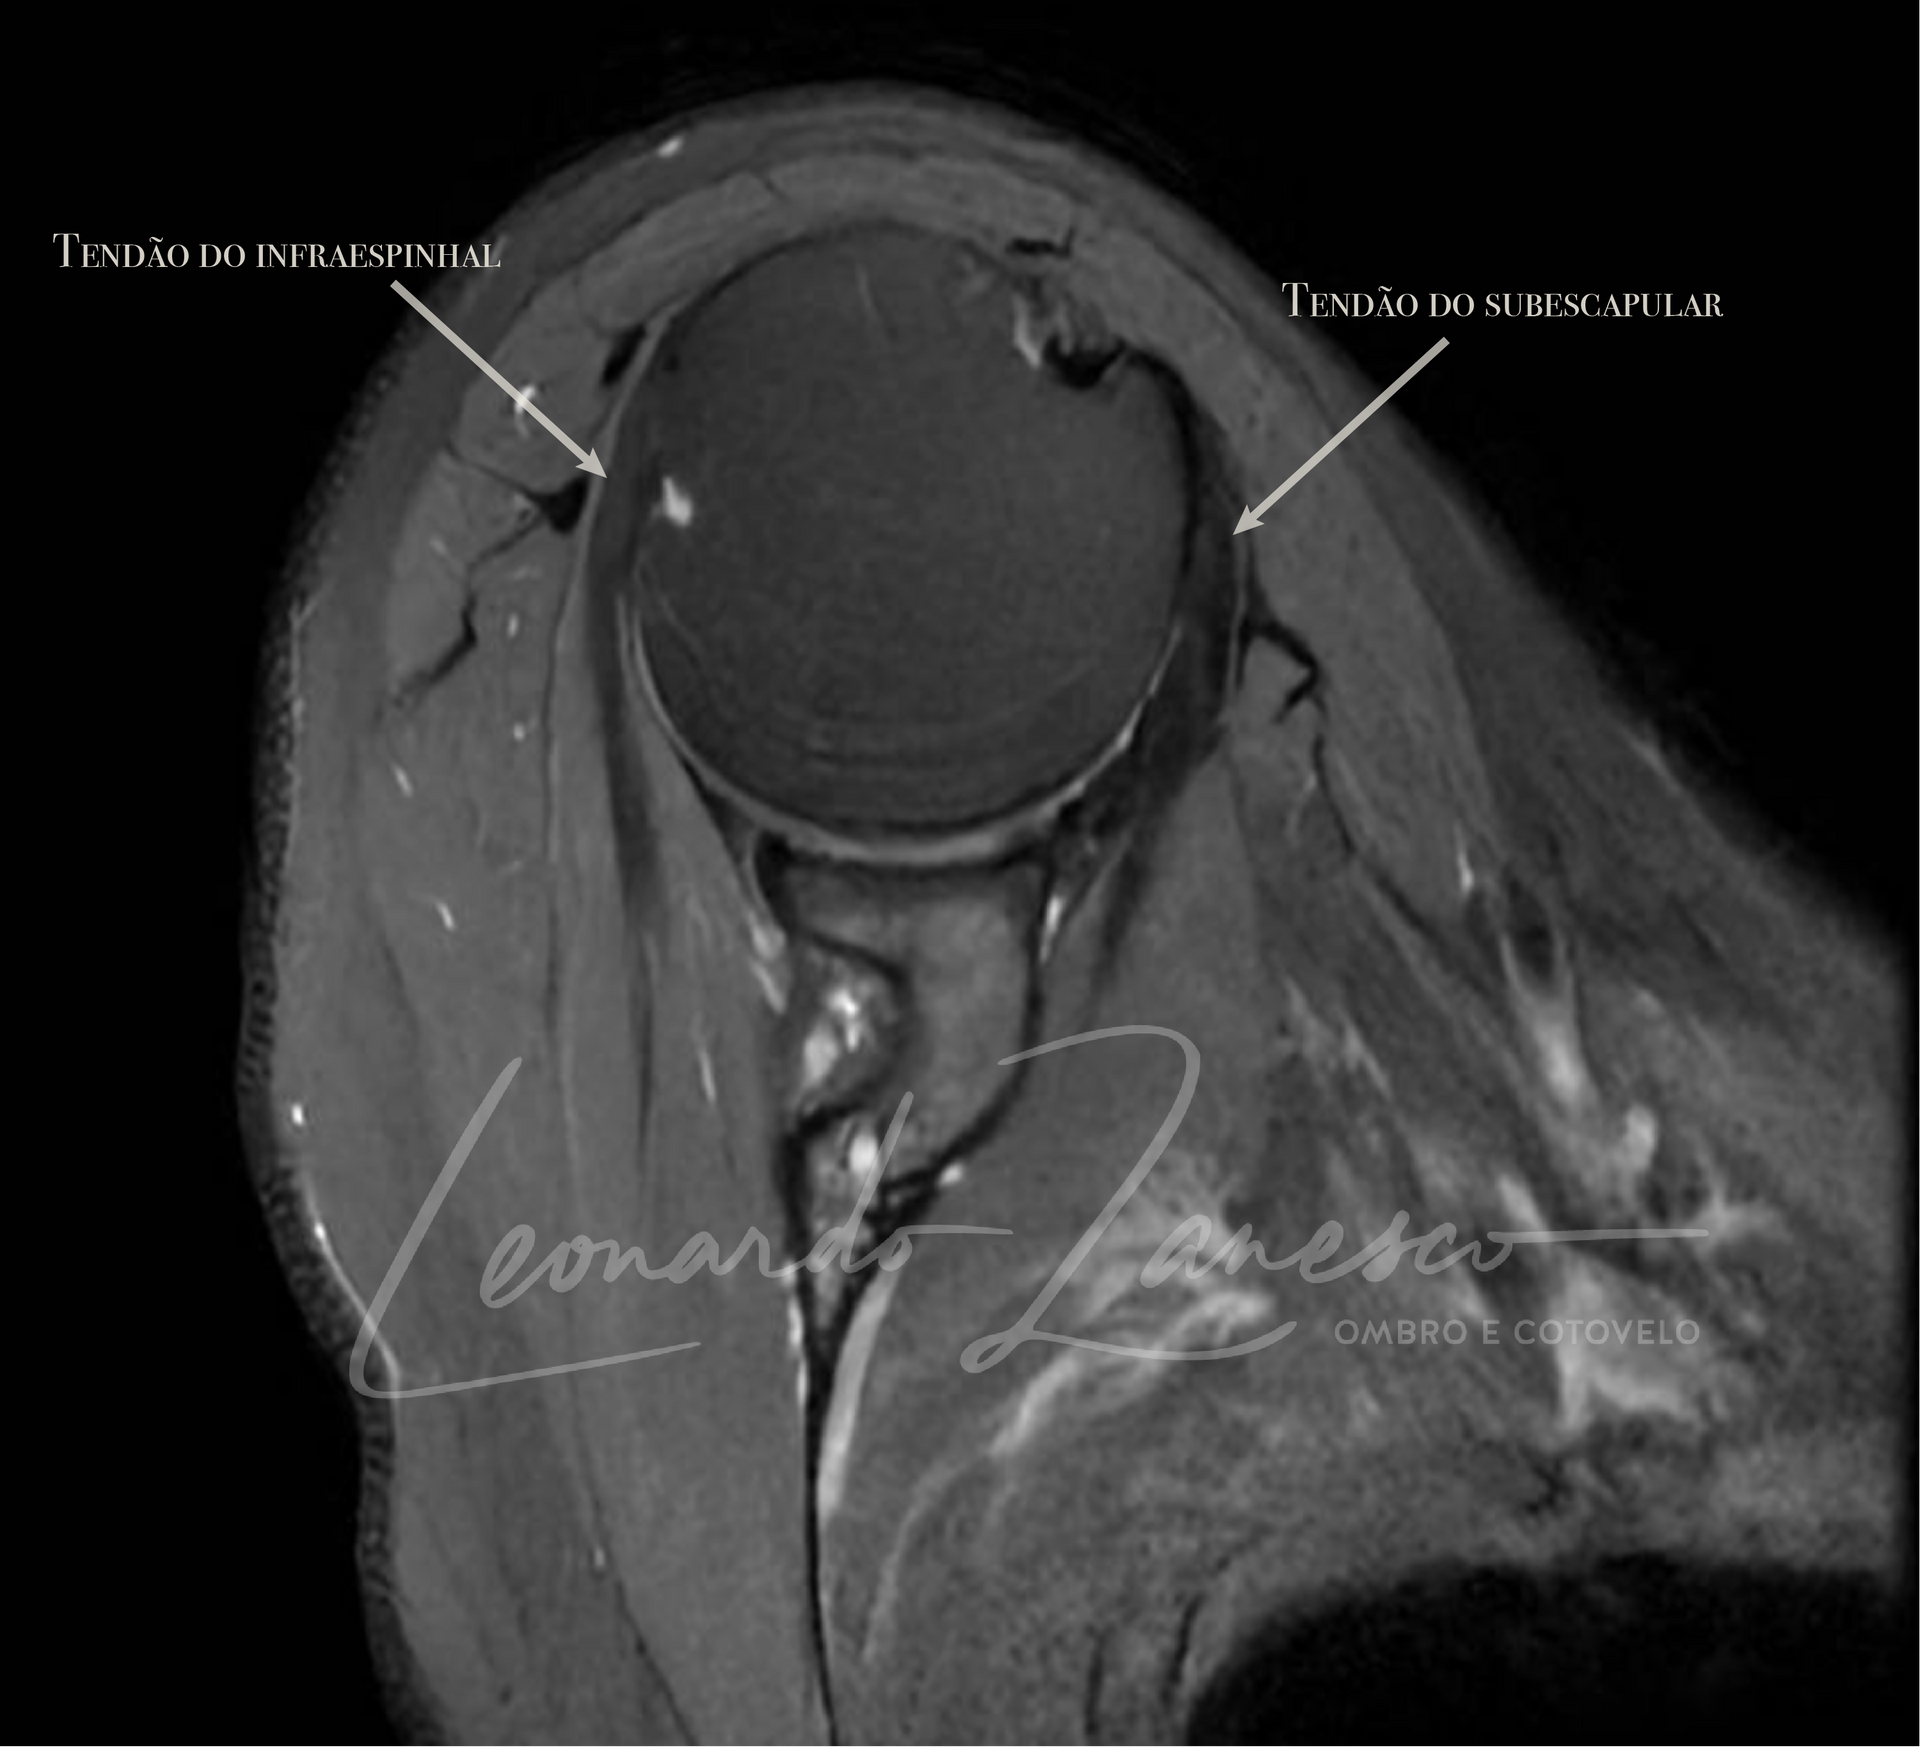

O manguito rotador é uma estrutura complexa composta por quatro músculos e seus tendões que envolvem a cabeça do úmero (o osso do braço), estabilizando a articulação do ombro. Esses músculos são essenciais para a movimentação e estabilidade do ombro, permitindo uma ampla gama de movimentos coordenados. Os músculos que compõem o manguito rotador são:

- Infraespinhal: Situado na parte posterior do ombro, este músculo permite a rotação externa do braço. Ele trabalha em conjunto com o redondo menor para realizar movimentos rotacionais externos e estabilizar a articulação durante atividades como arremessar e levantar objetos.

- Subescapular: Encontrado na parte anterior do ombro, o subescapular é responsável pela rotação interna do braço. Este músculo é o maior dos quatro e desempenha um papel vital na estabilização do ombro, especialmente durante atividades que envolvem empurrar ou puxar.

Sinais de ruptura incluem dor intensa, fraqueza significativa, limitação de movimento e estalidos no ombro. Exames de imagem como ressonância magnética (RM) confirmam o diagnóstico.